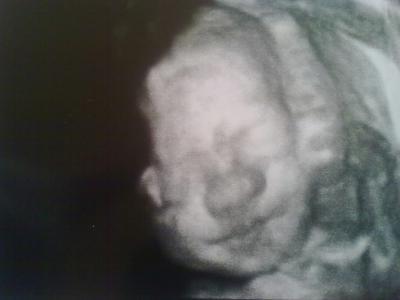

Ich hatte gestern meinen FA-Termin bei 25+6! Unser kleines Kerlchen ist super entwickelt und alles ist Bestens! Gestern lag er in SL...

Wer mag - Daten zum Vergleichen:

Größe: 32cm

Gewicht: 777g

Kopfumfang: 22,78cm

Bauchumfang: 20,42cm

Und ein süßes Bildchen von seinem Gesichtchen hänge ich euch auch noch dran!